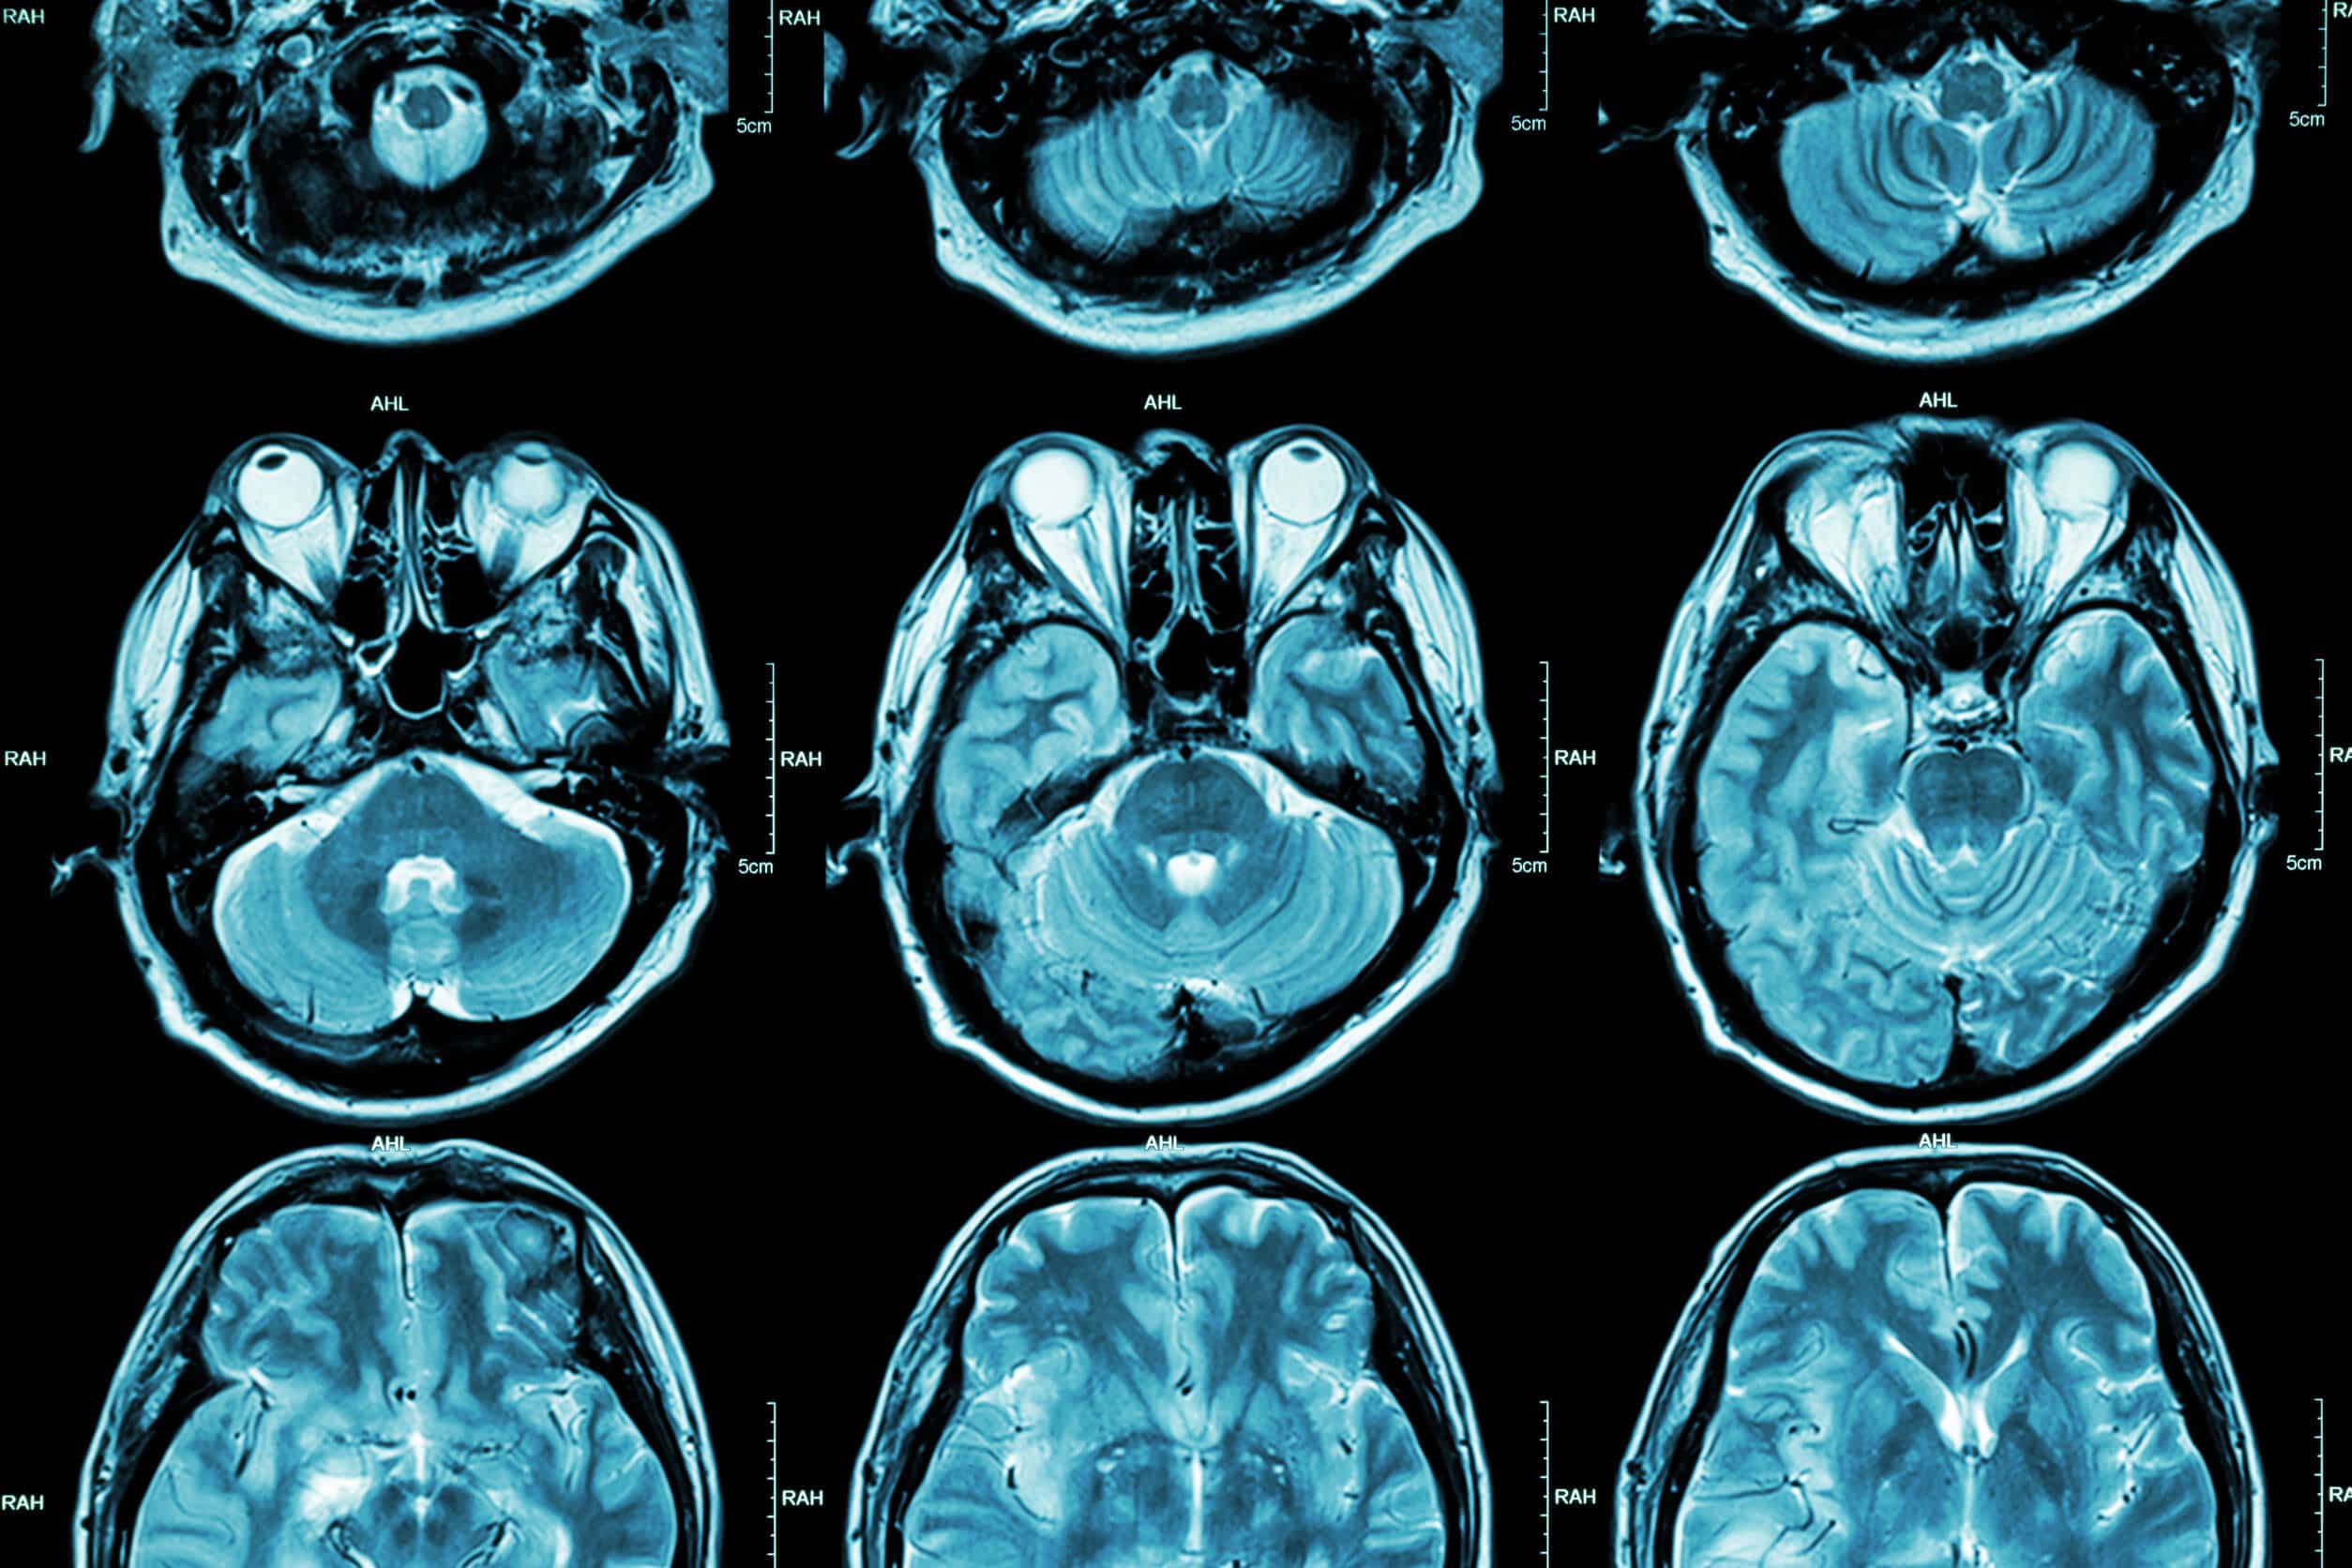

This case involved a fifty-one-year-old male with a twelve year delay in the diagnosis of acromegaly. The patient’s medical history included diabetes, two knee replacement surgeries, and significant dysmorphic facial features. Some of those features included an enlarged tongue, increased teeth spacing, and enlarged skull bones. Additionally, the man experienced chronic headaches unresolved by medication. During fifteen years of established care with his internist, no diagnosis of acromegaly was ever made. The patient was very self-conscious about his appearance and developed depression and anxiety over the last two years. He was especially displeased with difficulties achieving an erection with his wife. His interest in sex had also declined. Most concerning to the patient was that his blood glucose levels remained elevated regardless of good compliance with his diabetes medications. The patient was never referred to a specialist, nor was he ever spoken to about considering other less medically focused options such as sex therapy. One day, the patient developed a severe headache and loss of peripheral vision, which warranted a visit to the local emergency department. The hospital ordered an MRI of his brain, revealing a pituitary adenoma. To confirm the diagnosis, an IGF-1 level was ordered. Subsequently, a diagnosis of acromegaly was made.

The internist properly diagnosed diabetes in this patient; however, he was unable to properly manage it. He should have either investigated other causes of diabetes or referred him to an endocrinologist. If he chose to manage the patient on his own, he should have ruled-out the diagnosis of acromegaly as a cause of uncontrolled diabetes. The single best test used to diagnose acromegaly is insulin-like growth factor 1 (IGF-1). If the results of IGF-1 are unequivocal, serum growth hormone (GH) should be measured. Another important test ordered for the diagnosis of acromegaly is an oral glucose tolerance test. Patients with acromegaly will fail to suppress serum GH levels following the administration of glucose. Besides these screening modalities, patients will present with physical features that are very indicative of acromegaly. These would include enlarged hands and feet, enlarged tongue, teeth spacing, enlarged jaw and skull bones, coarsening of facial features, and sexual dysfunction. Acromegaly is usually due to a pituitary adenoma, which is a neoplasm of the pituitary gland that produces excess levels of growth hormone. This finding can be seen in MRI. This enlargement can cause headaches and peripheral vision loss in patients. Pharmacologic treatment of acromegaly usually involves octreotide, a somatostatin analog that suppresses growth hormone levels. If the adenoma grows to a larger degree or the octreotide fails to work, the patient will require transsphenoidal removal of the adenoma.